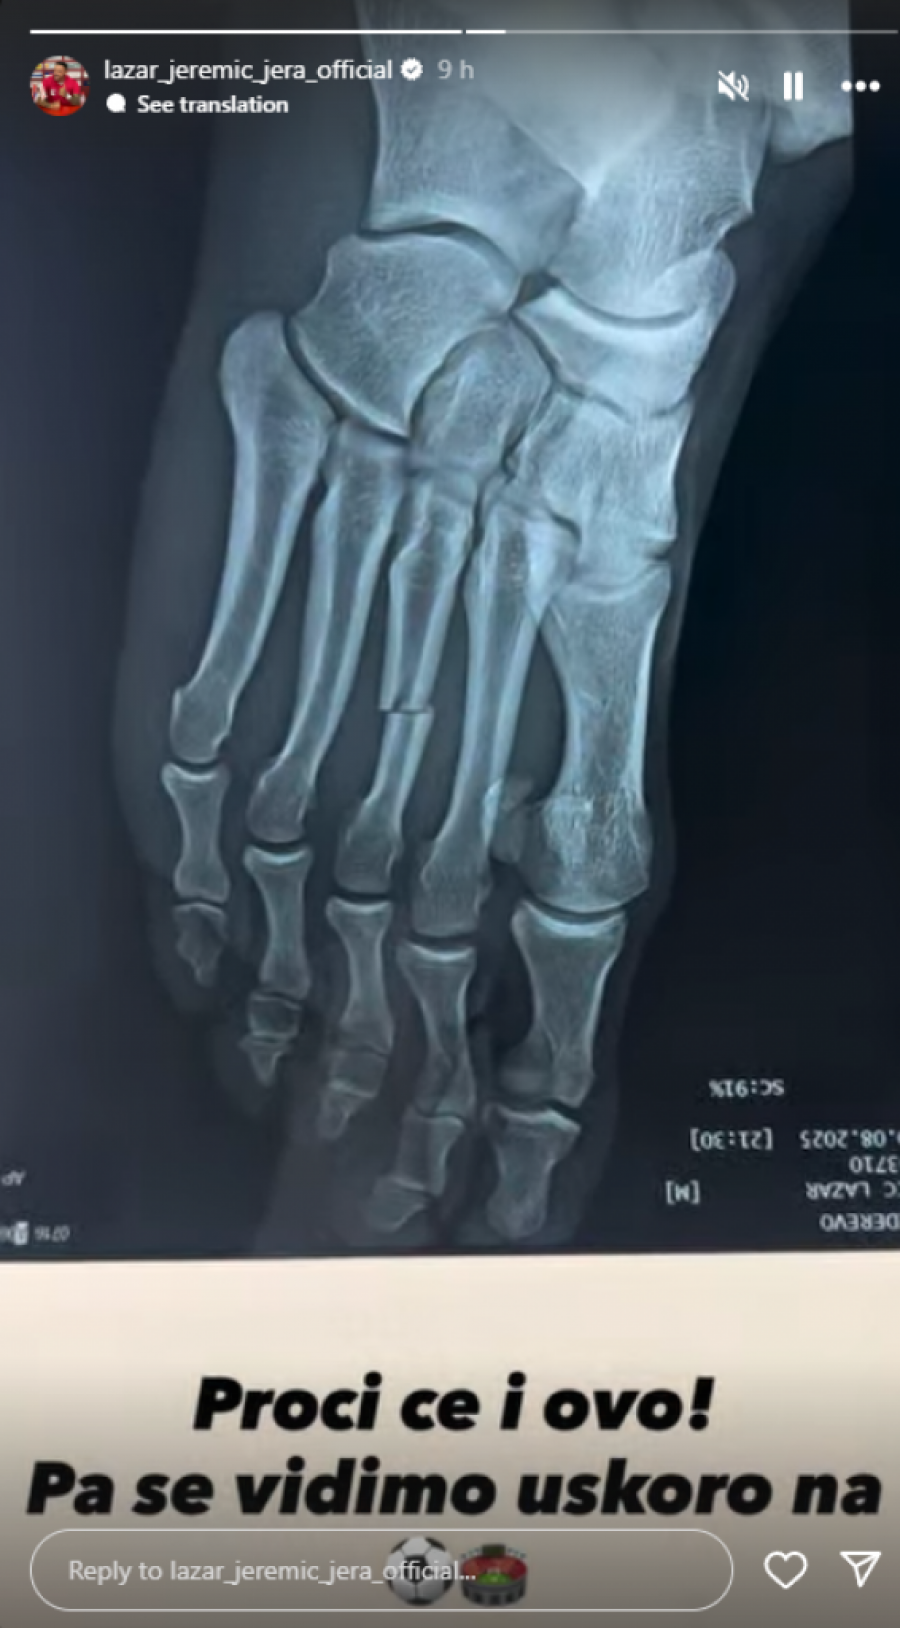

Bivši rijaliti učesnik Lazar Jeremić nedavno je izazvao pažnju svojih pratilaca na Instagramu objavivši snimak iz bolnice. Na snimku se vidi kako leži na bolničkom krevetu sa nogom u gipsu, što je odmah izazvalo brigu među njegovim fanovima. Jeremić je u opisu snimka objasnio da mu je kost pukla na dva dela, što će značiti da će njegov oporavak trajati duže od očekivanog. Ova situacija nije nova za njega, jer je već ranije imao operaciju zbog koje je dugo odsustvovao iz svoje fudbalske karijere.

Zanimljivo je da Lazar nije stranac povredama. Njegova prethodna operacija, koja je rezultirala dugim oporavkom, ukazuje na to da se povrede u sportu često dešavaju, ali i na to koliko su ozbiljne. Fudbal je fizički zahtevna igra, a povrede su nažalost deo svakodnevnice mnogih sportista. Lazarova trenutna situacija naglašava koliko je važno brinuti se o svom zdravlju i rehabilitaciji, kako bi se povratak na teren uspešno ostvario.